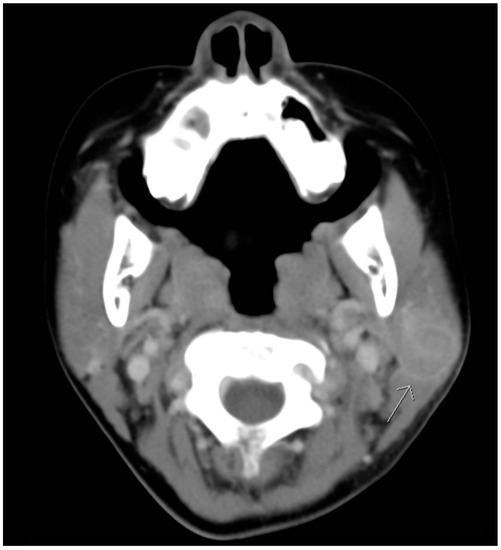

Although defervescence was observed on the seventh day after admission, the size of the mass was stationary. On the third day of hospitalization, azithromycin was prescribed based on the positive results of Mycoplasma pneumonia IgG and IgM serological tests. Nevertheless, the mass remained unchanged with prominent tenderness. Furthermore, a new round mass was observed on the ipsilateral part of the neck, which was located approximately 5 cm lower than the first mass; the size of this newly emerged mass was 2 × 2 cm2 and it was also hard, tender with well-defined margin. Computed tomographic (CT) scanning of the head and neck was therefore arranged, which revealed lymphadenopathy in the bilateral necks and a hypodense cyst with ill-defined margin in the left parotid gland. (Figure 2 and Figure 3). Based on the radiographic findings, a mumps virus immunoglobulin M (IgM) serology test was conducted.

Figure 3. Transverse computed tomographic view revealing a hypodense cyst with ill-defined margin in the left parotid gland. (arrow head).